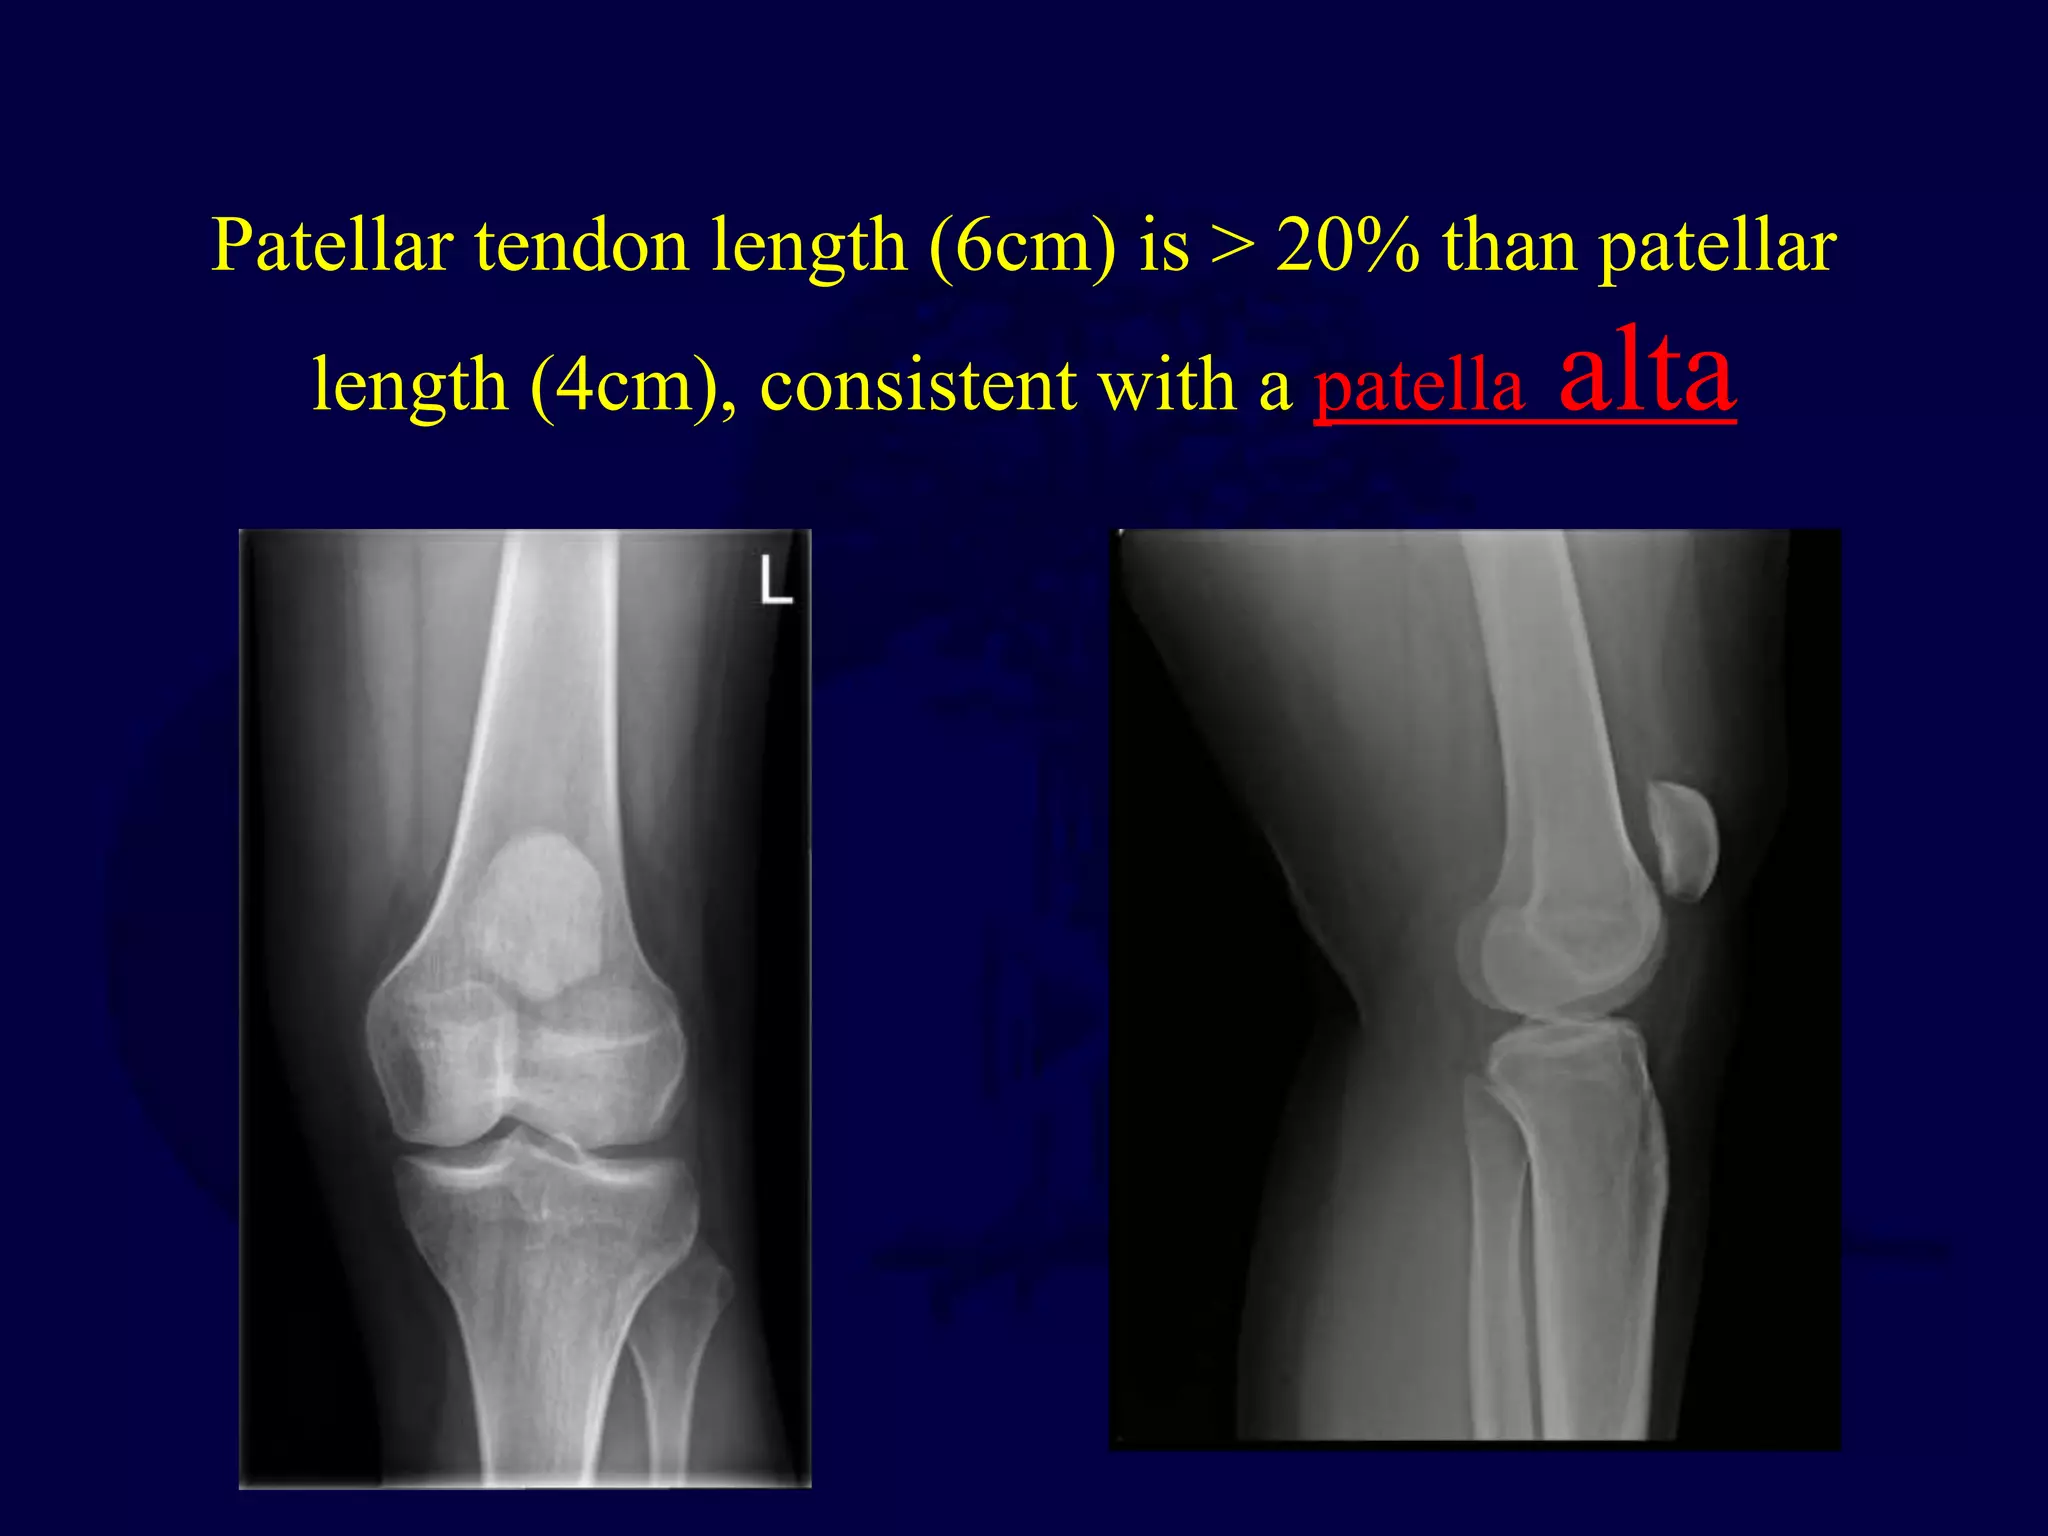

Patellar tendon length (6cm) is > 20% than patellar

length (4cm), consistent with a patella alta

Patella alta

• high riding patella, describes a situation

where the position of the patella is

considered high. It may be idiopathic or

may result secondary to a patellar tendon

rupture.